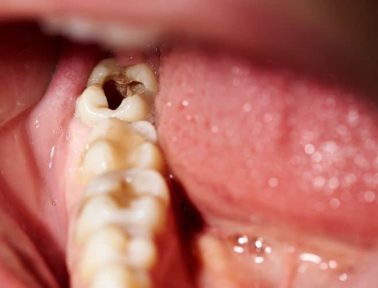

Oct 03

Tooth decay, also known as dental caries or cavities, is a very common oral health issue that can have far-reaching consequences, if left untreated. It can lead to other oral health concerns and is linked to general health conditions.